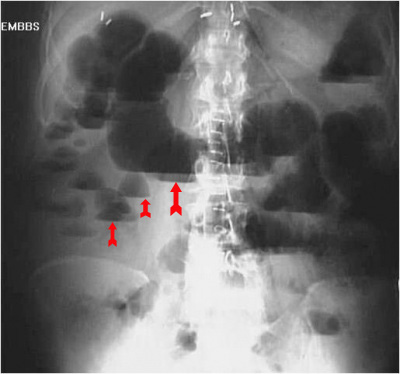

בצילום בטן סקירה ניתן לראות חסימות דינמיות, התרחבות של המעי הדק (תצלום 1.4), ופלסי אוויר נוזל במרכז הבטן המסודרים בצורת מדרגות (תצלום 2.4). הוולבולה קוניובנטס מודגשים לרוחב הרירית (תצלום 3.4).